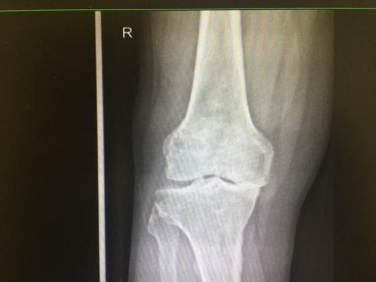

2.以膝关节骨性关节炎为例

在对尸体与手术活体的观察中,发现膝关节表面软骨在压力和磨损下,部分表面软骨消失,关节间隙变窄,但关节表面破坏的再严重也看不到骨刺。而在其边缘有肌腱牵拉的地方却有明显的骨刺形成,有的甚至构成骨桥。

10.骨性关节炎:早期或中期关节间隙无狭窄,或轻度狭窄

11. 膝关节内翻,内侧间隙变窄,但屈伸不受限